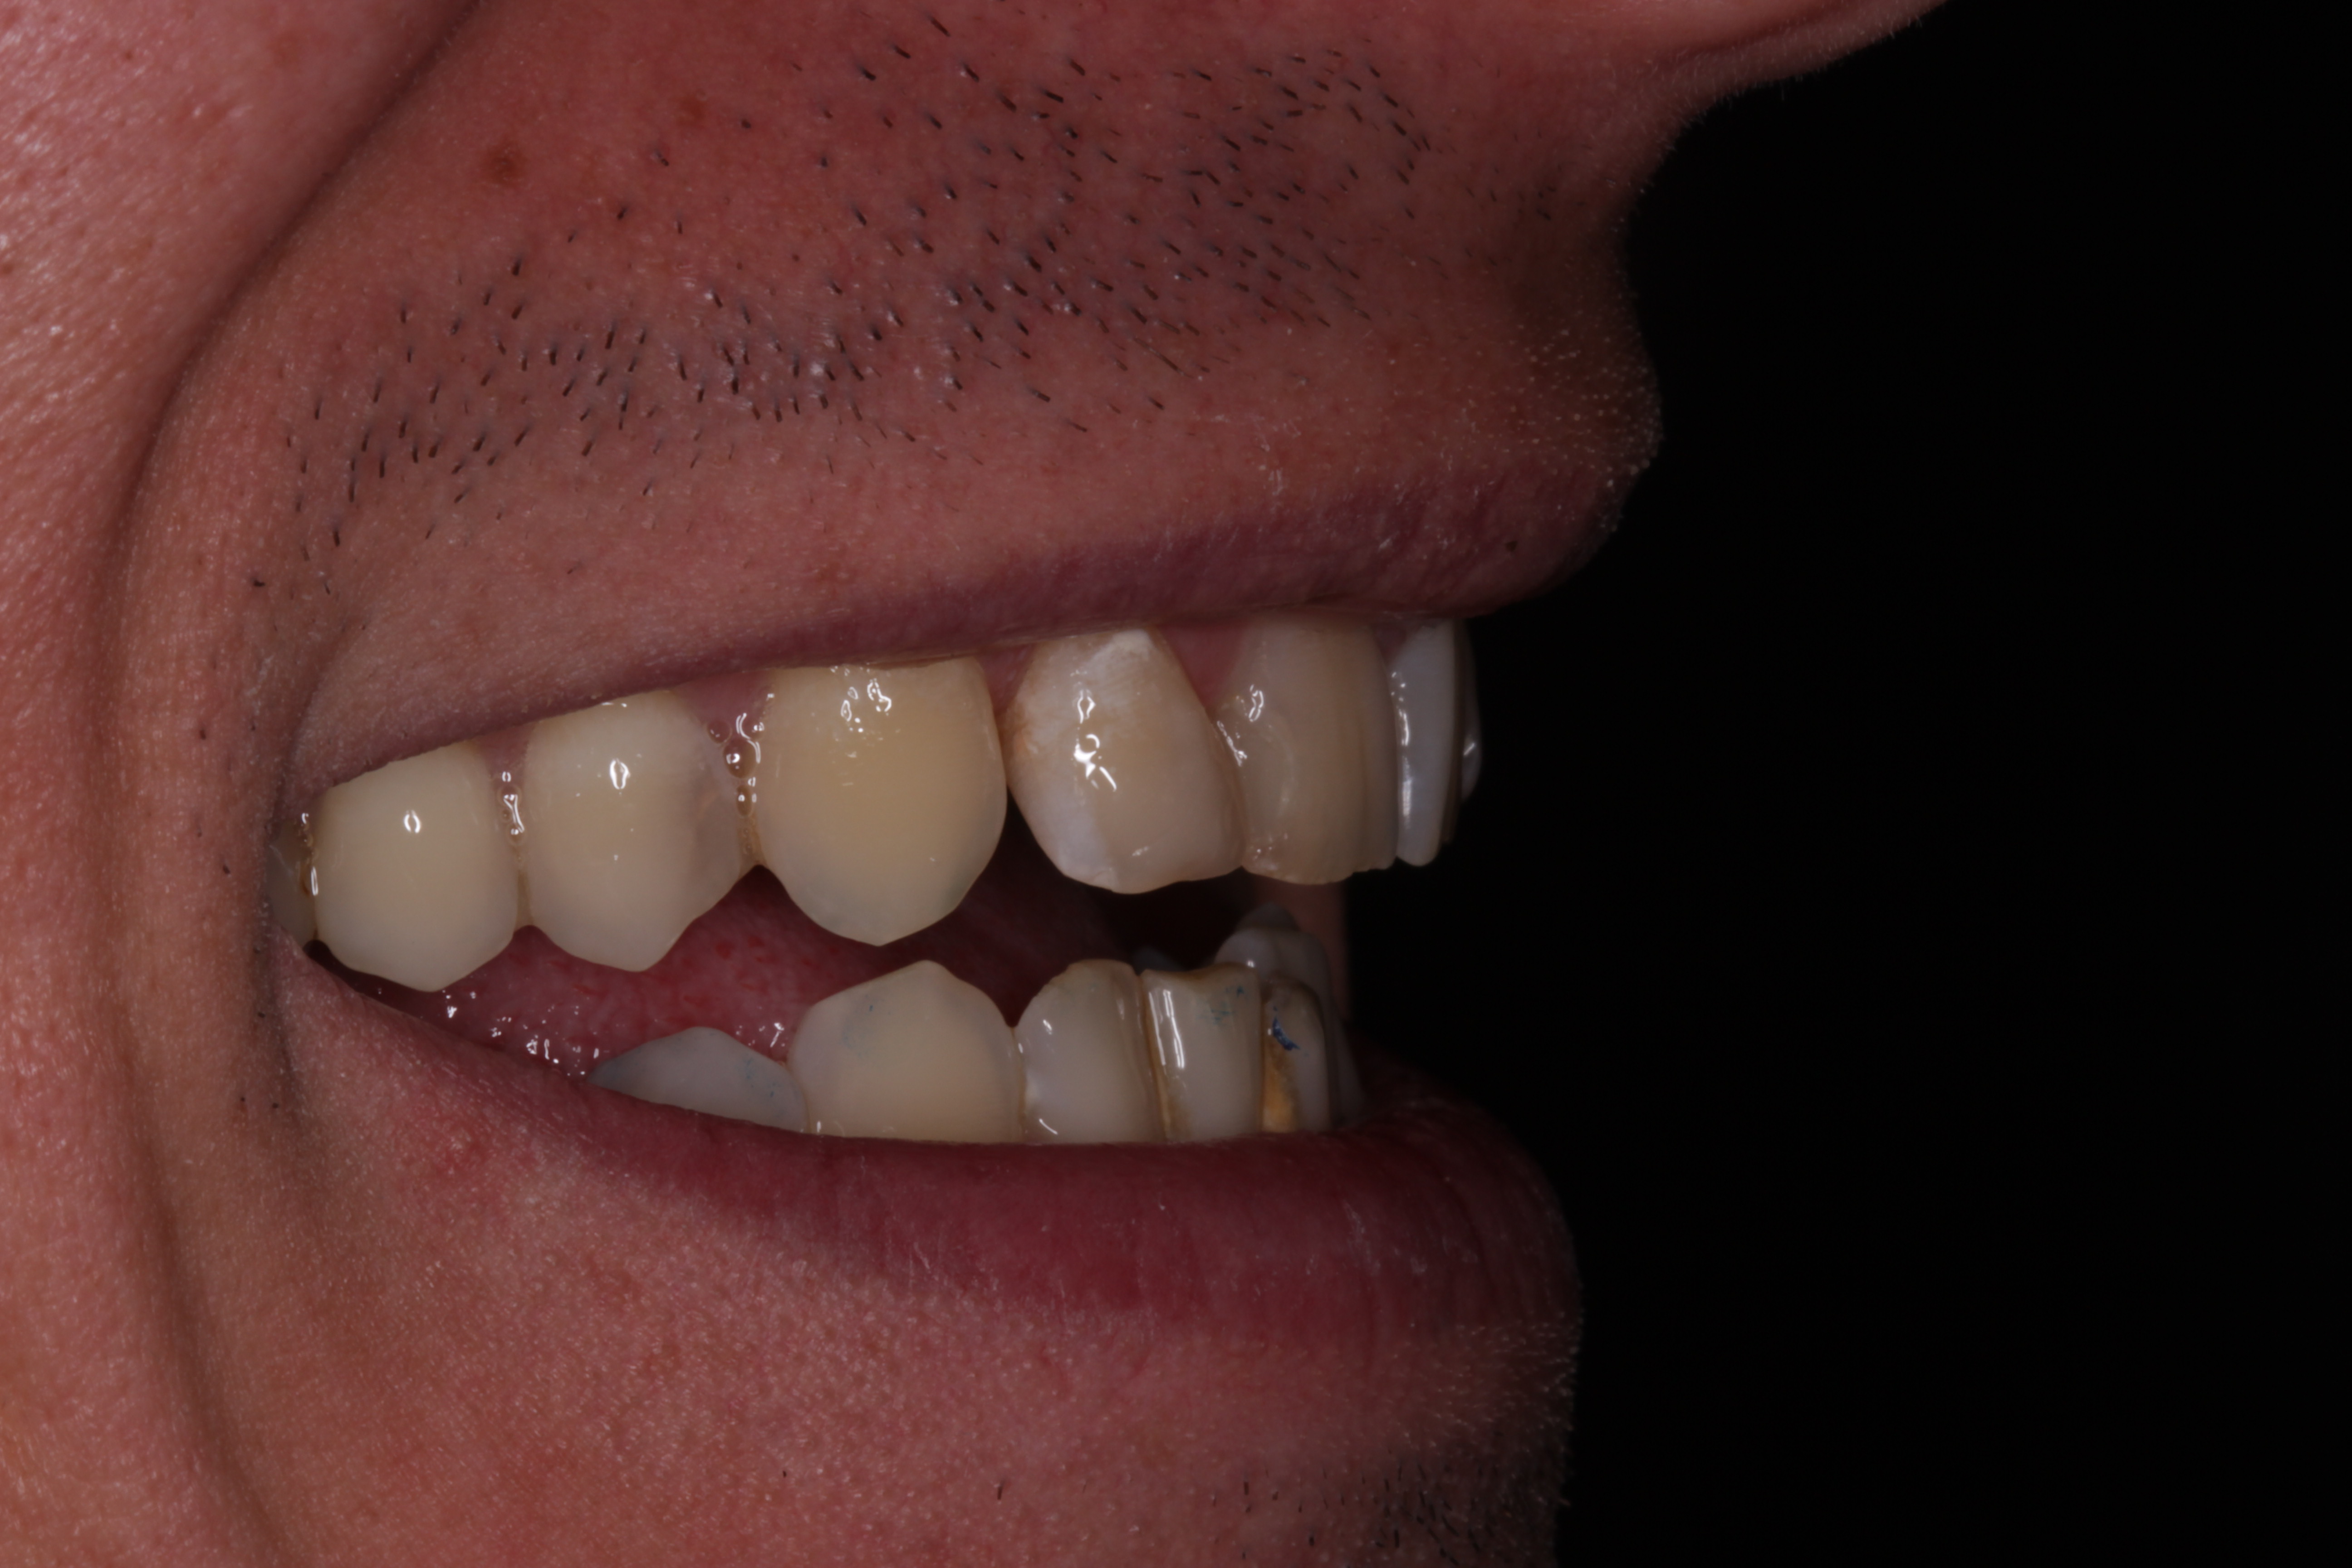

- Rehabilitación postraumática